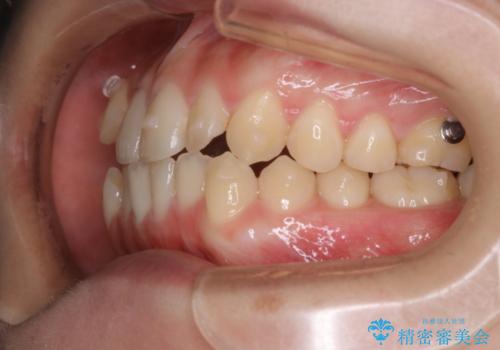

- 非抜歯、インビザライン治療希望の患者様です。

右の犬歯が八重歯になっており、通常であれば抜歯を選択する可能性が高くなりますが、

マイクロインプラントと呼ばれる骨に打ち込むネジを使用し、非抜歯での治療計画を立てました。

マイクロインプラントを使用することで非抜歯での治療が可能となりました。

マイクロインプラントを使用せずに無理に非抜歯治療を行った場合、

治療後に出っ歯になってしまうなどの問題が起きる可能性が高いです。